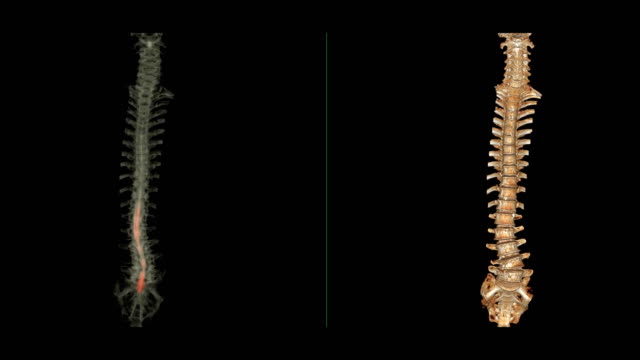

척추관협착증에 대한 이해

척추관협착증은 척추 주변의 근육과 인대가 퇴행하여 척추관 내 황색 인대가 비정상적으로 부풀어 오르면서 발생하는 퇴행성 척추질환 중 하나입니다. 이 질환은 가까운 거리도 통증으로 인해 걷기가 어려워지는 특징을 가지고 있으며, 새벽에 다리에 통증을 느끼는 경우가 많습니다.